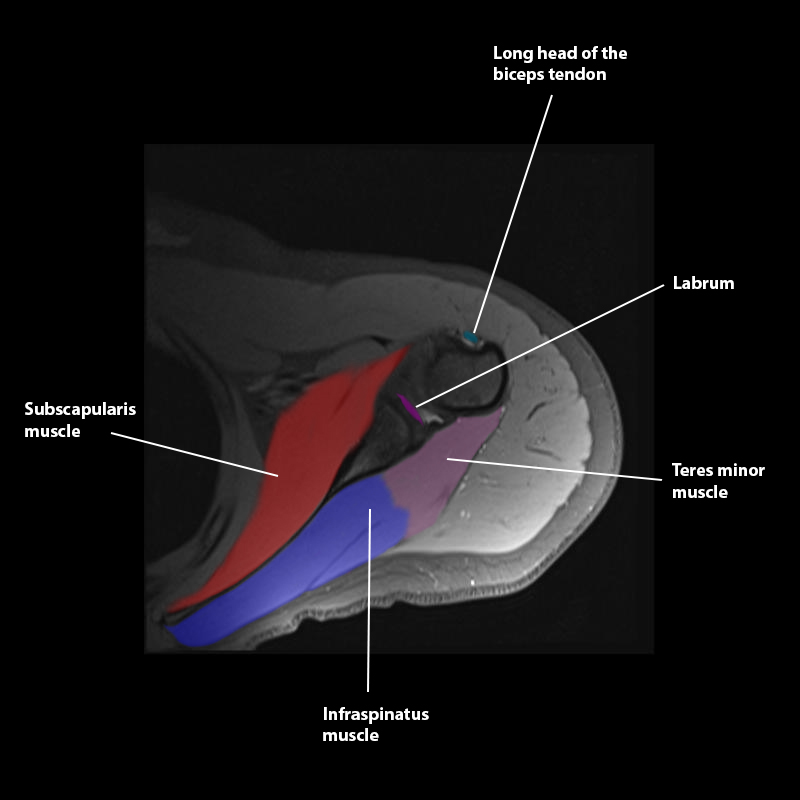

Shoulder MRI Anatomy